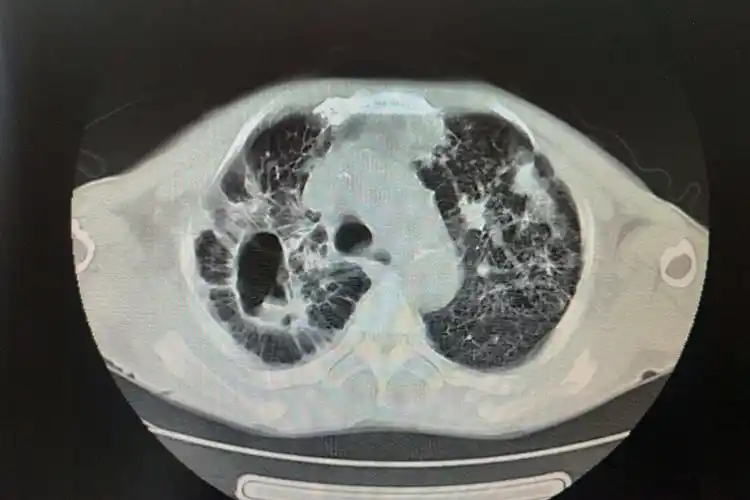

亚急,慢性血行播散型肺结核图

空洞型肺结核ct图片